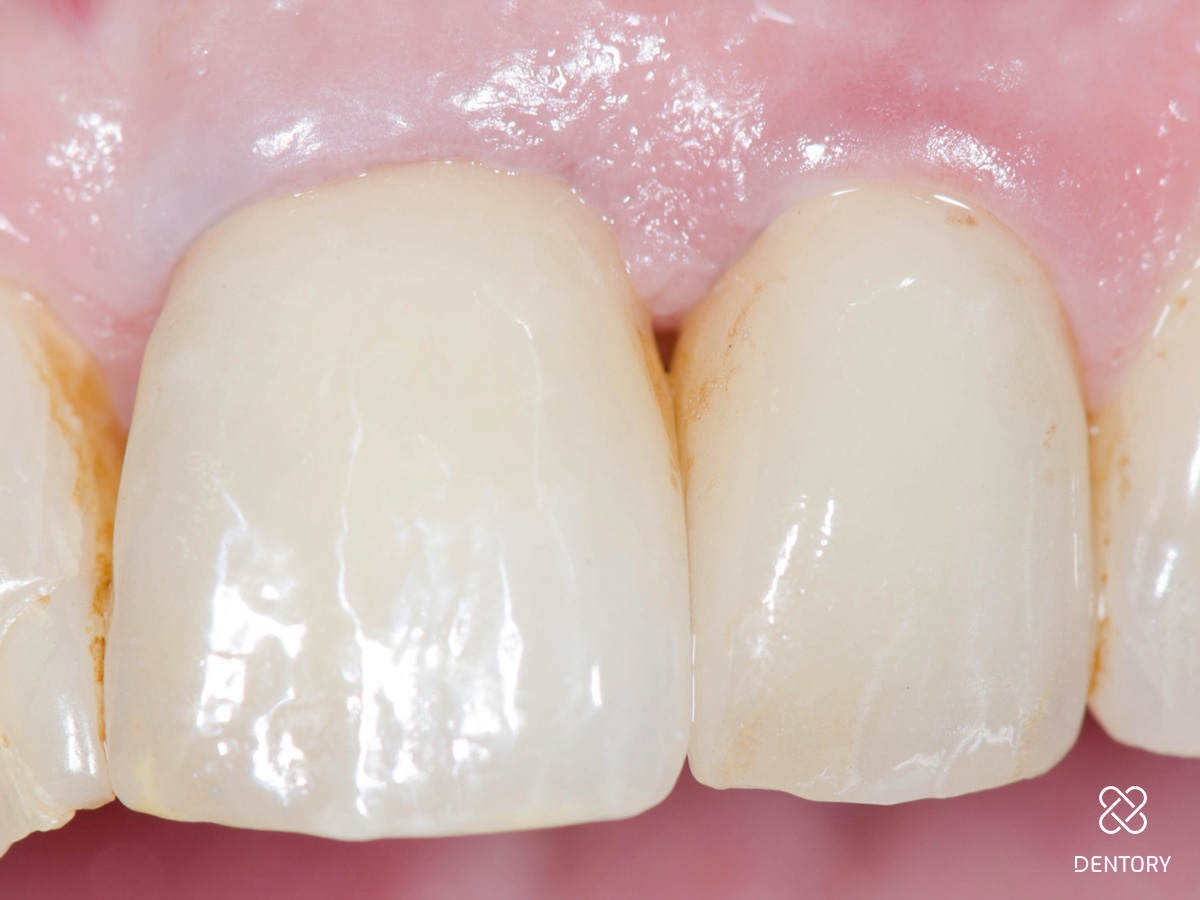

Abbildung 11

Abschluss: Klinische Situation nach dem vollständigen Aushärten des Zements und dem Entfernen der Überschüsse.

Abbildung 12

Abschluss okklusal: Fertige Situation von okklusal.